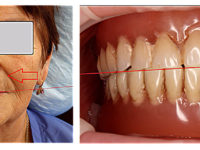

На фото представлен клинический случай в котором гребень практически полностью атрофирован, его попросту нет… В таких случаях, еще на этапах диагностики, необходимо учитывать те факты, что возникнут проблемы не только с фиксацией протеза на челюсти, но и возможные боли при ношении. Так как мы наблюдаем обнажение нерва в пределах протезного ложа, в мягких тканях нижней челюсти.

Проведя расчеты на основе ТРГ, мы обнаруживаем что нижняя челюсть данной пациентки имеет дистальное положение, следовательно когда происходит регистрация центрального положения на основе восковых шаблонов, должно быть принято решение в каком соотношении производить протезирование, оставить данное либо найти другое..